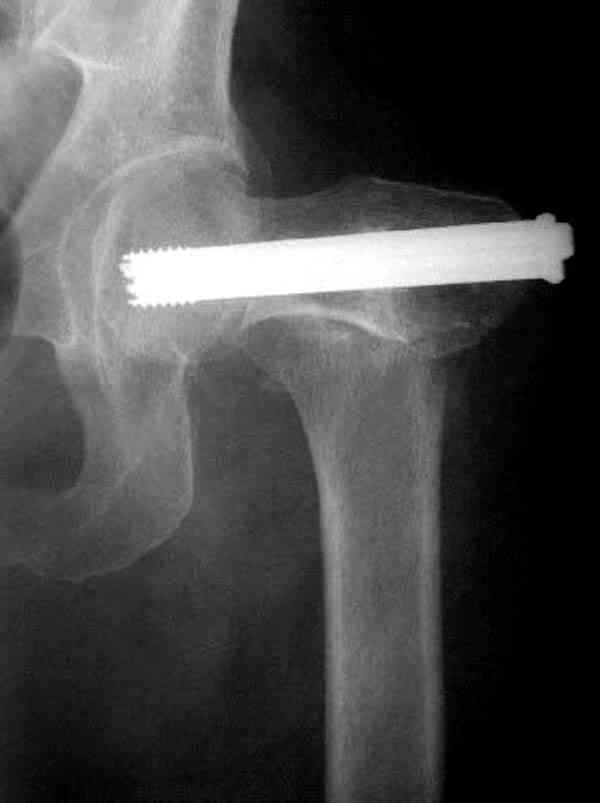

Коллега Челноков прав, здесь еще имеется риск перелома за счет ослабления латерального кортекса. Во время установки канюлированных шурупов за редким исключением спица вводится с одного раза, множественные попытки ослабляют латеральный кортекс, что станет источником перелома в этом месте.

В идеале для профилактики рефрактуры шурупы надо вводить не больше, чем под 130 градусным углом и не ниже уровня малого вертела.

Насчет биомеханических преимуществ одного шурупа тоже возникает вопрос. Если придерживаться канонов механики, для перелома шейки необходимо 3 паралельных шурупа, расположенных ближе к кортикальному слою шейки.

Здесь случай перелома из-за ослабления латерального кортекса через 3 недели после операции на шейке. Шурупы были установлены под большим углом, слабый латеральный кортекс не выдержал нагрузку.